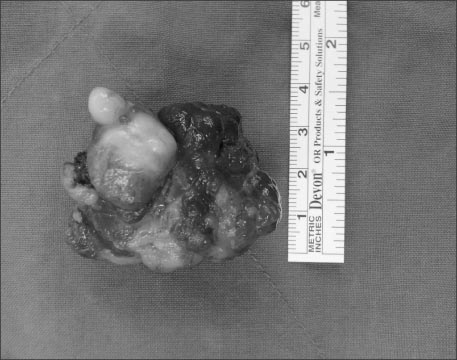

An ultrasonographic scan showed no remarkable abnormal findings. Upper gastrointestinal endoscopy revealed a 3 cm-sized polypoid mass with bleeding at the lesser curvature of the upper gastric body (

Fig. 1). At first, we planned to carry out an endoscopic polypectomy, but the polyp had such a large base that the polypectomy could not be performed. Therefore we chose to carry out an open laparotomy instead.

Fig. 1Endoscopic finding shows multi-lobulated polypoid mass with oozing at upper body of stomach.